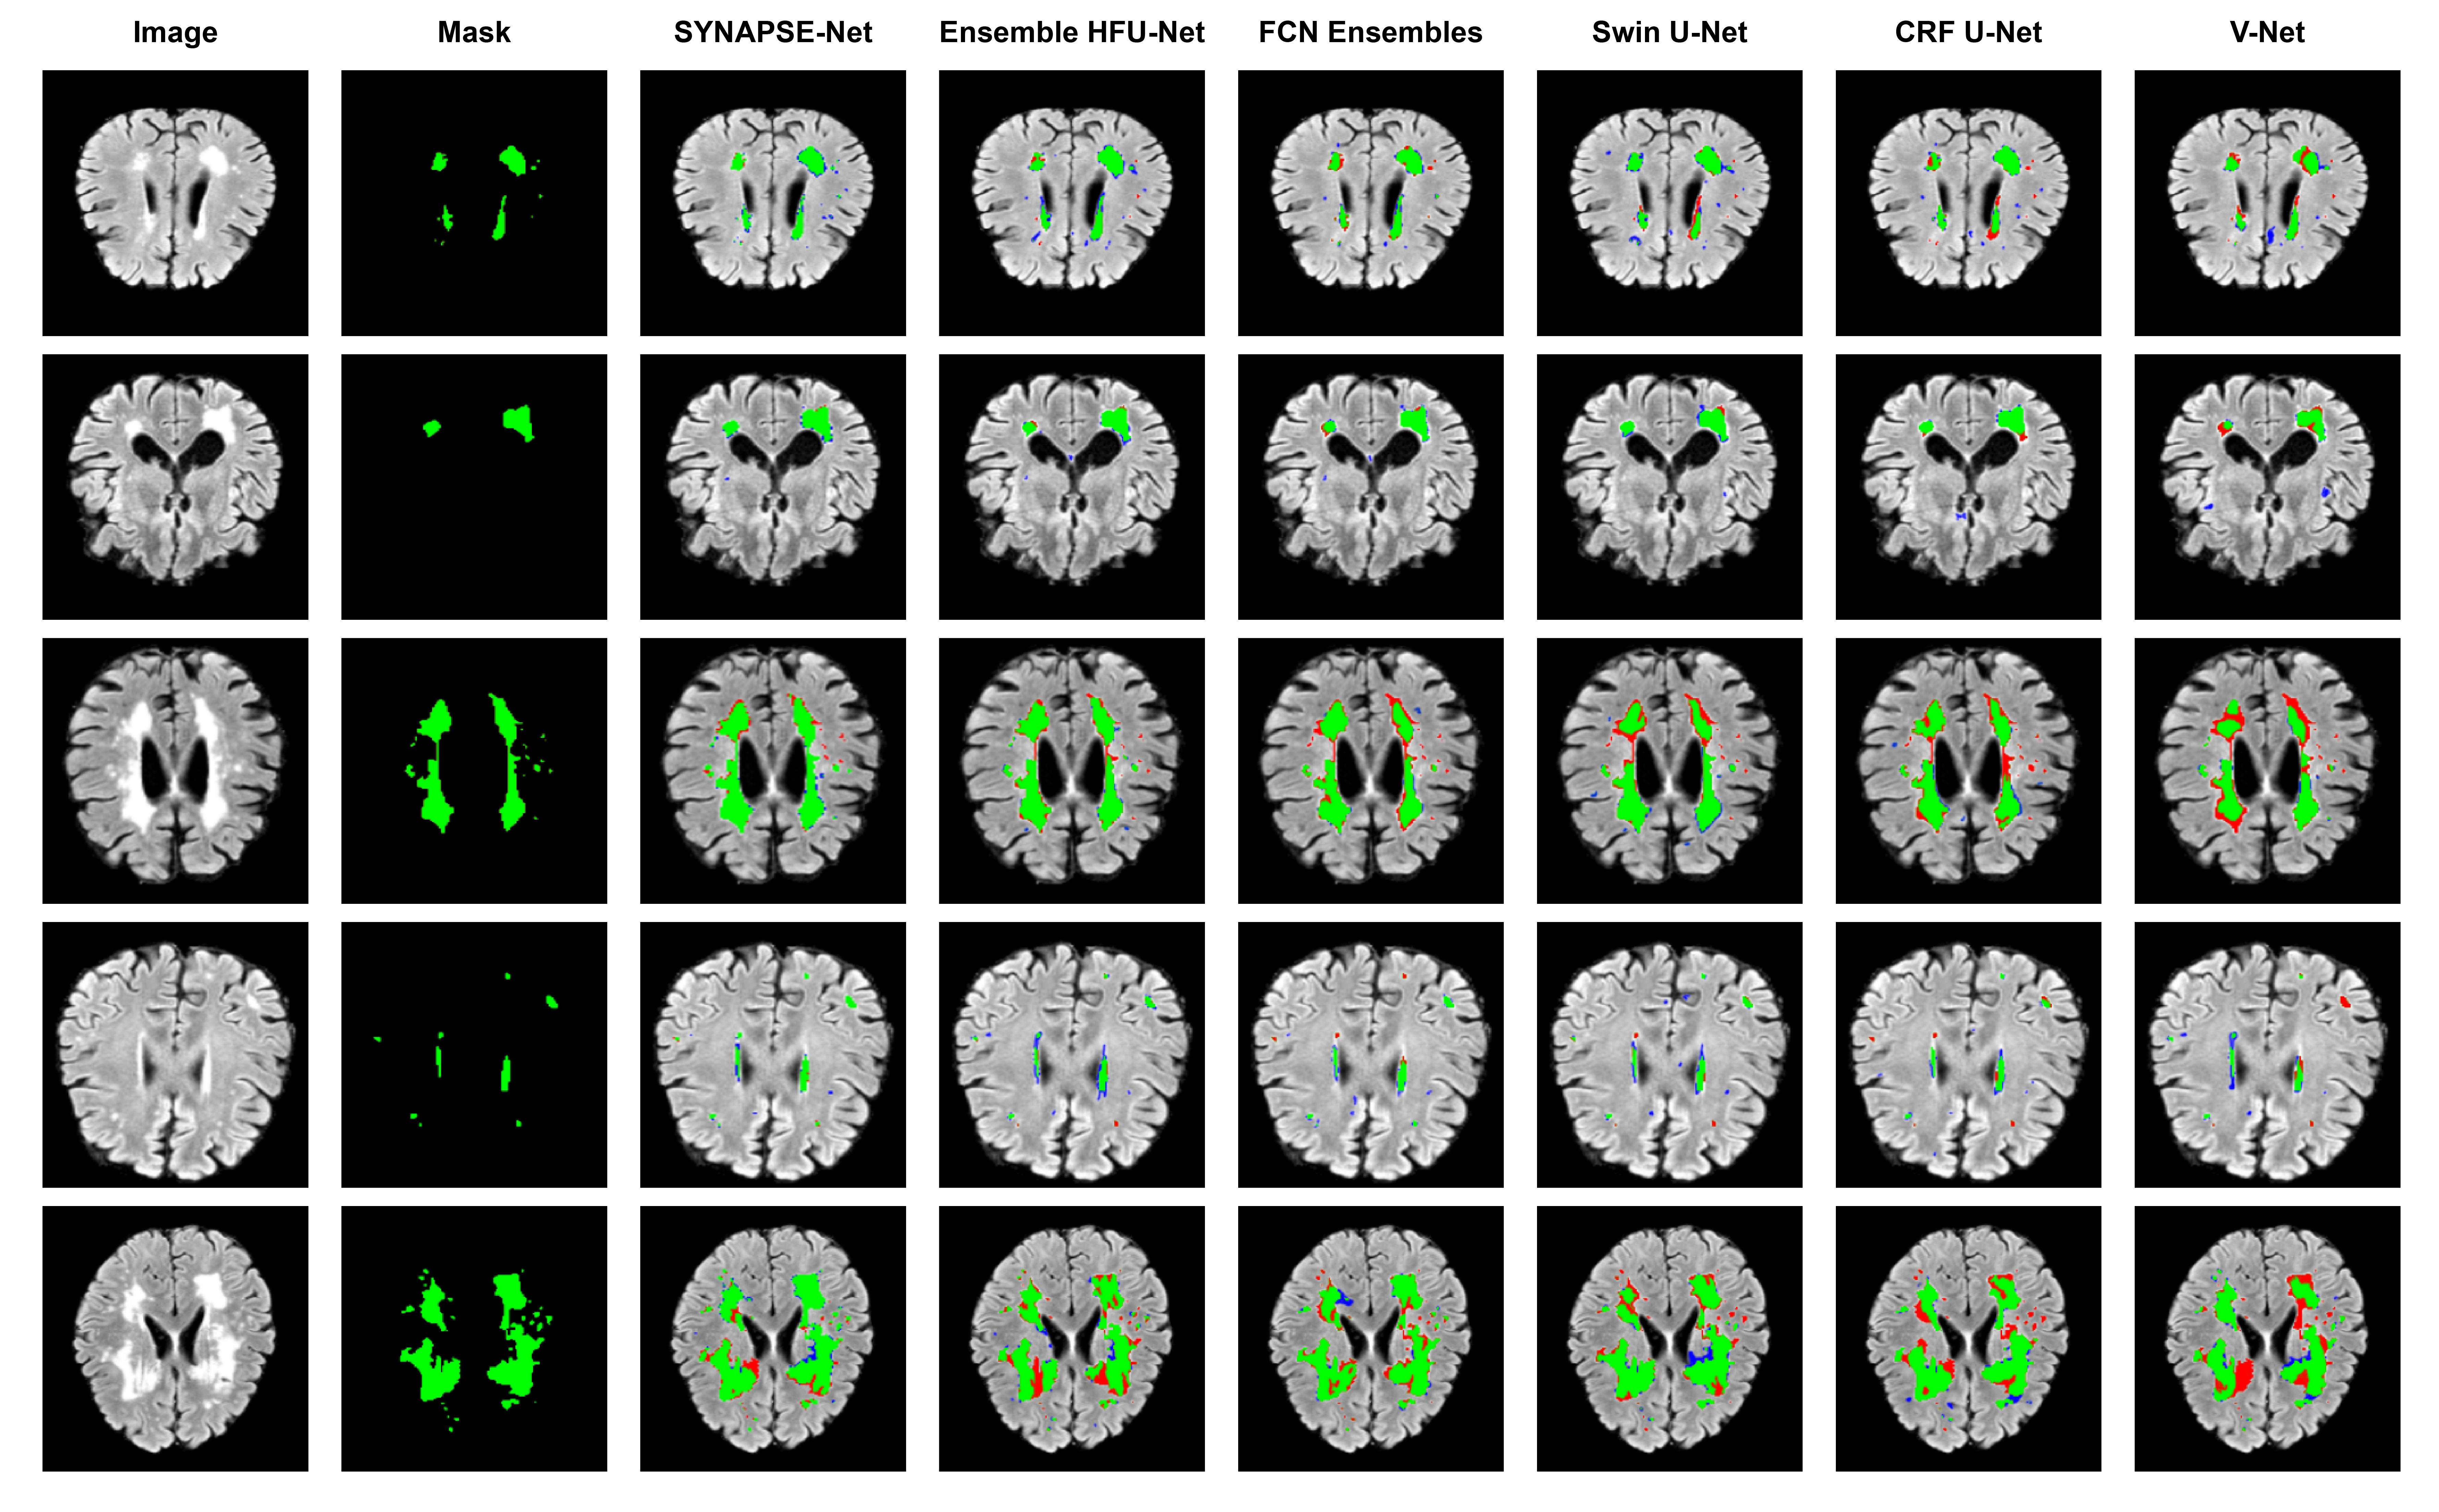

Refer to caption

Figure 8: Qualitative comparison on the ISLES 2022 dataset. Green (True Positive), Red (False Negative), Blue (False Positive).

Our proposed framework demonstrates robust lesion detection with a recall of 0.84. Although Attention SwinU-Net (He et al., 2025) achieved a higher recall of 0.92, this came at the cost of a lower DSC of 0.72, indicating over-segmentation. However, our SYNAPSE-Net achieves this high recall while maintaining the highest DSC, which proves the ability of our model to find the vast majority of lesions without sacrificing segmentation accuracy. Furthermore, SYNAPSE-Net delivers this state-of-the-art performance with just 13.46M parameters, making it more efficient than other high-performing models such as Swin U-Net (28.8M). It is visual in rows of small lesions (rows 1 and 4 of Fig. 7), where our system identifies almost all small satellite lesions, in contrast to those of competing methods such as Ensemble HFU-Net and FCN Ensembles. Such detection robustness and higher boundary detection competence in Table 6 validate the performance of our method for WMH segmentation.

3.6.2 Ischemic Stroke Segmentation Performance

We evaluated the performance of SYNAPSE-Net on acute vascular lesions against a diverse set of strong baselines and state-of-the-art models. Table 7 compares our approach with several established methods: nnU-Net (Isensee et al., 2020), ResU-Net (Jin et al., 2018), UNETR (Hatamizadeh et al., 2021), Swin UNETR (Hatamizadeh et al., 2022), and Ensemble UNet (Li et al., 2018).

Our evaluation demonstrates that SYNAPSE-Net delivers superior performance, attaining the highest DSC of 0.7632 and F1 score of 0.7420. Ensemble UNet maintains a competitive DSC of 0.7580 that does not differ significantly from ours, but its F1 performance (0.7088) is notably lower. In contrast, ResU-Net presents comparable F1 of 0.7385, which is statistically not significant from our model, although its DSC (0.7207) remains substantially lower. The most distinct advantage of our framework lies in boundary accuracy. Achieving an HD95 of 9.69, SYNAPSE-Net surpasses Ensemble UNet by 33.6% and ResU-Net by 38.6%. This substantial margin underscores the effectiveness of our hierarchical gated decoder and cross-modal fusion mechanism in preserving geometric fidelity. Furthermore, SYNAPSE-Net achieves these results with only 13.46M parameters. This demonstrates enhanced efficiency compared to larger models like ResU-Net (28.86M) and UNETR (42.47M), while outperforming the more compact Ensemble UNet (8.8M) in critical boundary-aware metrics.

This advantage in boundary accuracy is visually validated in Fig. 8. In cases of large and complex infarcts (rows 1 and 4), comparison models such as Swin UNETR and DenseNet (Huang et al., 2017) exhibit under-segmentation along gyral boundaries, which correlates with their suboptimal HD95 scores. Conversely, our model generates a precise segmentation that closely follows the ground truth contours. The second and third rows illustrate smaller, subtle cortical and subcortical strokes where other models struggle. For instance, while Ensemble UNet achieves high recall, it is prone to scattered false positives. In contrast, our model yields a more coherent segmentation with minimal artifacts. The final row, representing a challenging cerebellar stroke, further highlights the robustness of our approach. Here, models like DenseNet and ResU-Net suffer from substantial inaccuracies, whereas our framework successfully delineates the lesion.